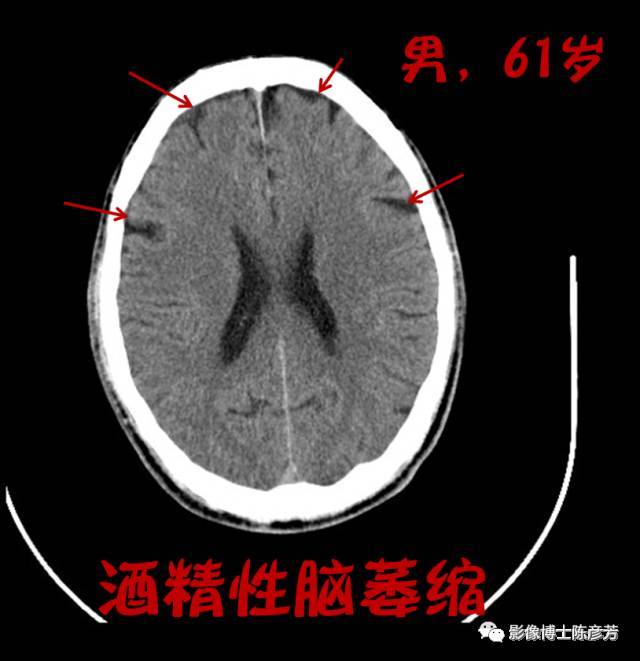

酒精性脑萎缩

酒精性脑萎缩,轻度脑萎缩

喝酒喝出脑萎缩,不是危言耸听!

脑萎缩ct

脑萎缩ct表现

脑萎缩ct图片

脑萎缩ct片子图片

脑萎缩ct图片解说